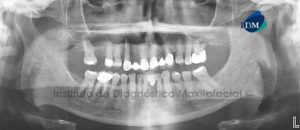

Paciente masculino de 20 años acude al Instituto de Diagnóstico Maxilofacial para evaluación imagenológica a nivel maxilofacial. A la evaluación de la radiografía panorámica se